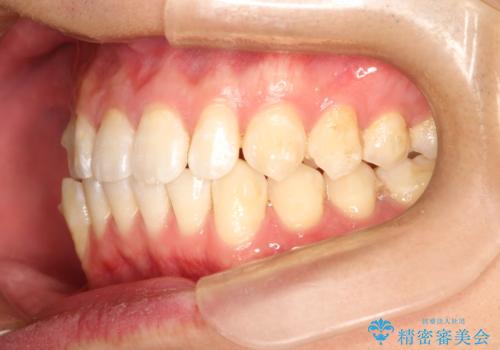

前歯がガタガタ インビザラインによる矯正

- 1年8ヶ月

使用時間を守っていただけたので、比較的スムーズに矯正を終了することができました。